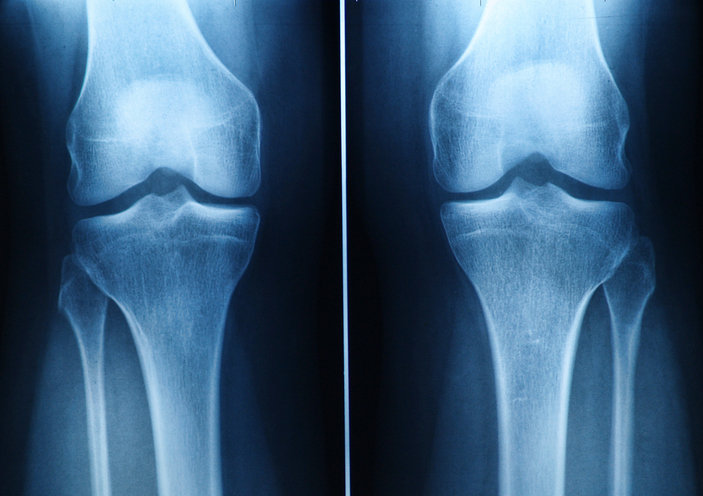

무릎 관절 엑스레이 사진. 사진=게티이미지코리아.